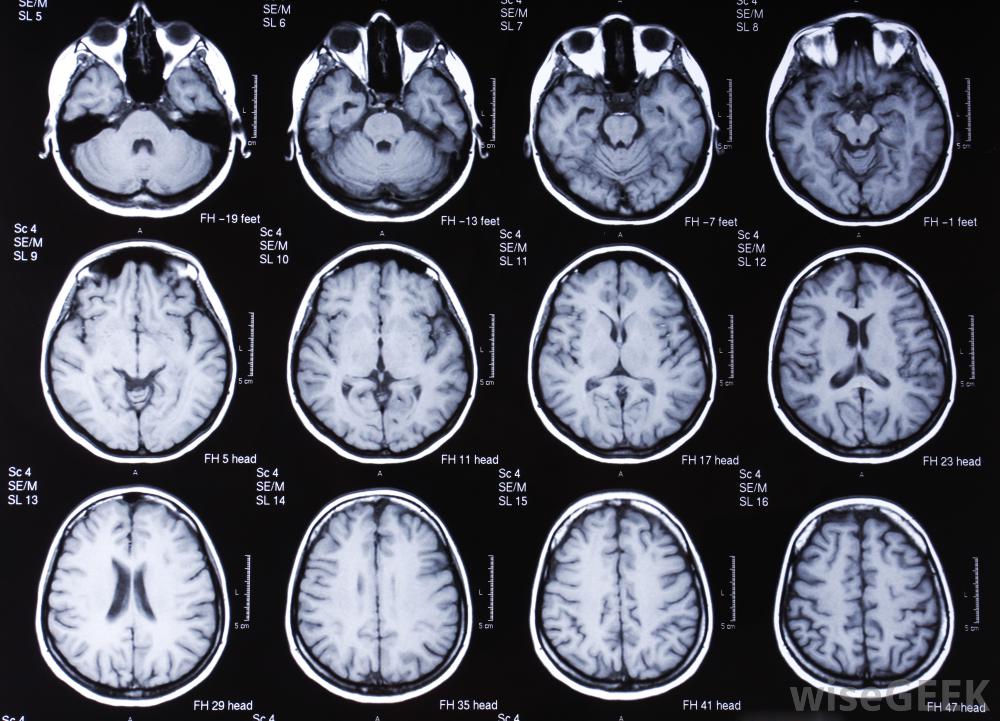

脑部的核磁共振扫描。

脑MRIs对研究者和医生都很重要。